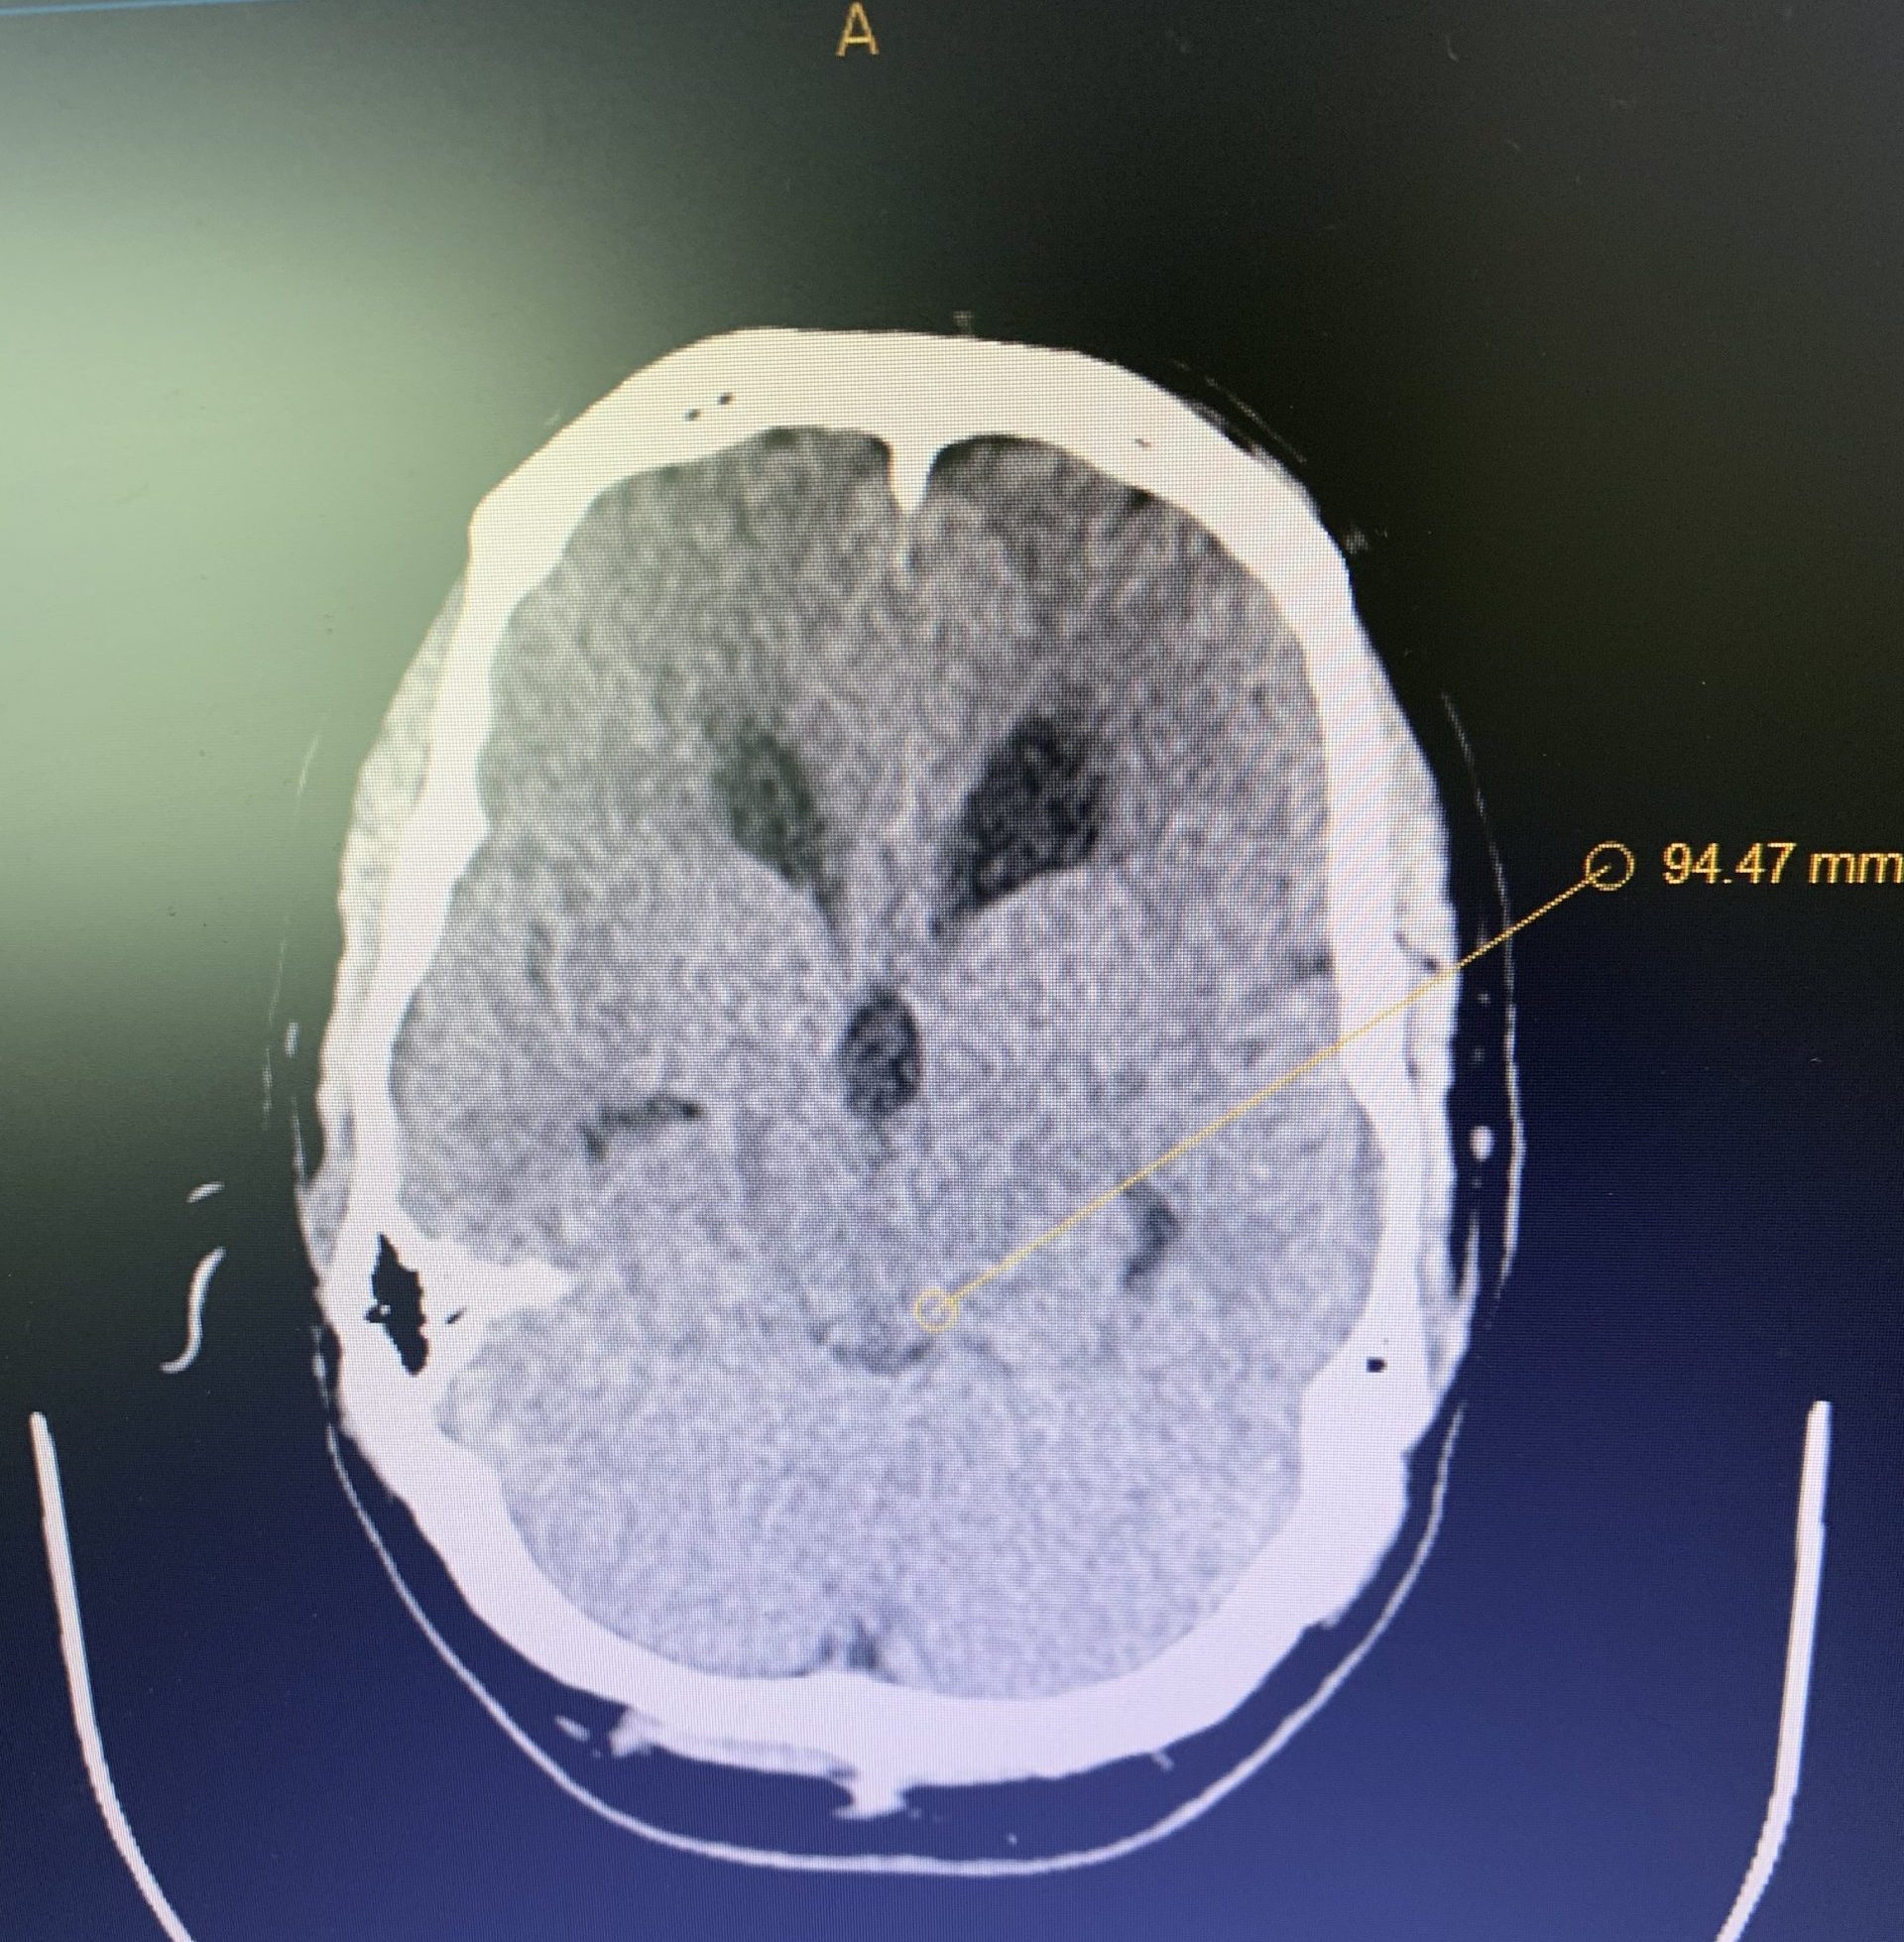

A young lady presented with a myriad of disabling difficulties, after a flourishing adolescence full of academic and athletic successes.

Her headaches, located on the top of her head, radiating to the neck and behind her eyes, were worse in the evening and made worse by standing. She had joint hypermobility (“double jointed”). Episodes of palpitations, postural orthostatic tachycardia, (POTS), and dysautonomia, severe nausea, difficulty swallowing, syncope, phonophobia, photophobia, and diplopia plagued this resilient soul.plagued this resilient soul. Despite this, she continued to work.

Imaging and other provocative diagnostic test showed the associated problems of Cranial Cervical Instability, incidental thoracic syringomyelia, Hashimoto Thyroidistis, Polycystic Ovarian Syndrome, Nutcracker Syndrome, Postural Orthostatic Hypotension, and Hypo/Hyper intracranial Pressure with spontaneous CSF leaks.

A formal diagnosis of Ehlers-Danlos Syndrome (EDS), a connective tissue disease, was made. There are 13 recognized types of this condition, both autosomal dominate and recessive. There is a broad range of presentations. Many, as in her case, are associated with many difficulties. Treatment is symptomatic and protracted.

Thankfully, marked improvement of her brainstem and lower cranial nerve function, demonstrated on trial cervical traction improved with Cranial-Cervical Fusion.